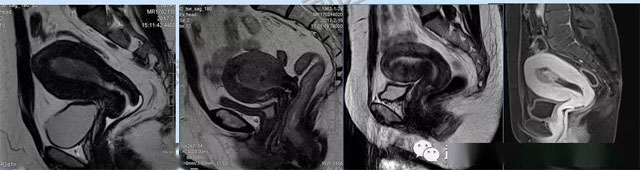

磁共振體檢車破解疑難婦科問題的關鍵工具

婦科疾病常常讓女性陷入了焦慮。主要是這類疾病婦女有難言之隱,癥狀隱匿,病情復雜。磁共振體檢車的金光火眼能力可以破解各種婦科難題。哪些情況需要使用磁共振檢查,檢查過程是否有不適。這些都是可以解決的。例如子宮常見疾病的磁共振診斷。

磁共振VS傳統檢查:有這些優勢?無輻射安全系數高,磁共振沒有電離輻射,適合備孕跟孕婦檢查。它對軟組織有高清的成像效果,可以清晰的看到子宮各層的結構。可以識別細小的肌瘤,早期的癌癥腫瘤??梢园l現其他設備難以檢查到的深部子宮內膜異位結節。多序列成像和增強掃描檢查,判斷腫瘤的良性準確率高達90%以上。

磁共振檢查可以對子宮內膜癌,精準測量腫瘤侵犯子宮肌層的深度,發現微小轉移灶。復雜子宮肌瘤明確肌瘤位置、數量,區分良性肌瘤與惡性肉瘤,幫助制定微創手術方案。卵巢腫瘤鑒別數值分析、增強掃描,可識別畸胎瘤、巧克力囊腫、惡性腫瘤的特征。宮頸癌分期,判斷腫瘤大小、是否侵犯膀胱/直腸,指導選擇手術或放化療。生殖道畸形三維成像直觀顯示畸形類型,為矯正手術或輔助生殖提供依據。